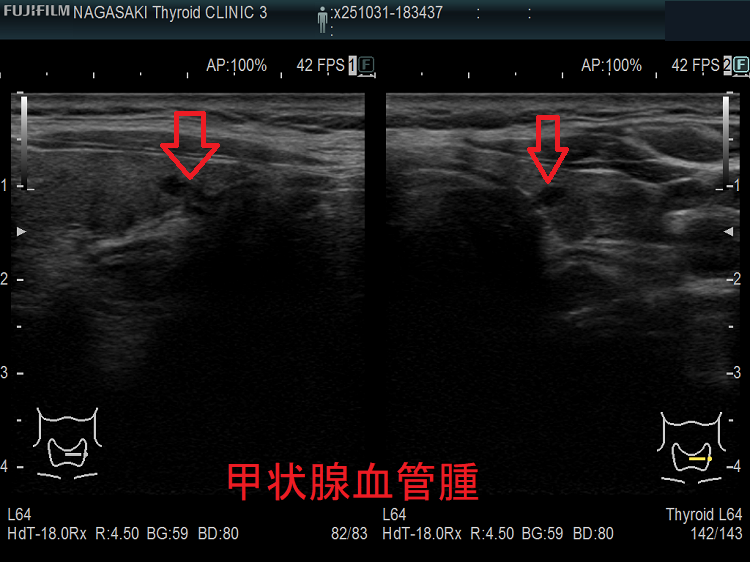

甲状腺に発生する血管腫は非常に稀で、日本の報告例もわずかです(日臨外会誌 72(3),579―583,2011)。

ケース①

ケース②

ケース③

甲状腺血管腫(拡大) ドプラーモード(eFlow);腫瘍内血管が3次元的に見え、毛玉の様。

ケース④

ケース⑤